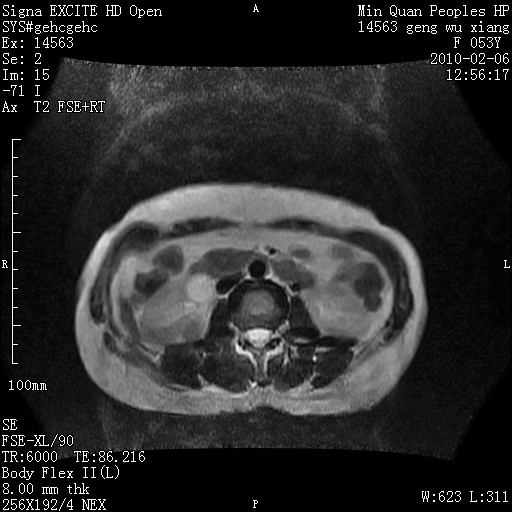

标题: MRI2762:胆道梗阻原因?

f,53y,全身黄染多日。

高位胆道梗阻 胆管癌可能性大

支持 高位胆道梗阻 胆管癌可能性大。